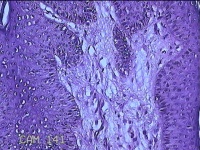

左侧会阴部结节

性别

女

年龄

43岁

临床诊断

皮肤良性肿瘤

一般病史

发现右侧会阴部结节3年余。

标本名称

大体所见

灰白粉红色带皮肤结节0.8x0.7x0.3cm一个,表面光滑,切开结节呈实性,切面灰白粉红色,质韧。